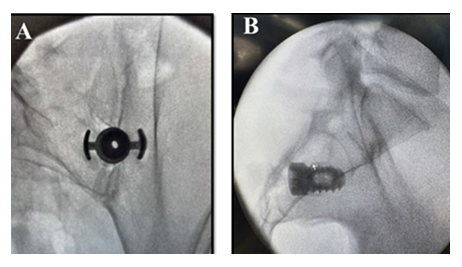

The current study involves the TiLink-P® posterior implant (Figure 1).

This novel and innovative 3D printed titanium posterior SIJ fusion standalone implant is designed with an open trellis (lattice) structure, a transfixing compression anchor, and Nanotex® (Bloomfield Hills, MI) surface technology. The implant is designed to transfix the ilium and sacrum while simultaneously compressing the sacroiliac joint to enhance stability and promote improved functional outcomes.

Patients were placed in prone position on a radiolucent table under general anesthesia or monitored anesthesia care (MAC). Multiaccess fluoroscopic guidance, including inlet oblique, outlet oblique, and lateral views were used. The SIJ was identified using the inlet oblique view. The entry point was identified below the inferior aspect of the posterior superior iliac spine and then an incision was made. Surgeons subsequently advance the guide pin into the joint, confirming trajectory with outlet oblique and lateral fluoroscopic views. A soft tissue dilator was placed over the guide pin down to the posterior margin of the sacrum using a lateral view. The drill guide was advanced over the dilator until firmly docked over the medial aspect of the ilium and the lateral aspect of the sacrum. The long tangs into the SIJ were confirmed with lateral, outlet oblique, and a gun barrel view. The soft tissue dilator and guide pin were removed. The drill was advanced through the drill guide to a positive stop thereby decorticating the joint while using outlet oblique and lateral views to confirm proper depth and trajectory. The drill was removed, and the implant inserter was advanced with the anchor wings down to a positive stop. At this point surgeons confirm the anchor transfixed the SIJ with outlet oblique and lateral views (Figure 2).

A hexalobe driver was used to deploy the screw to fixate and hold the anchor in place. Finally, the implant inserter was removed, and the joint was post packed with approximately 5cc of bone graft biologic material behind the TiLink-P® SIJ fusion implant.